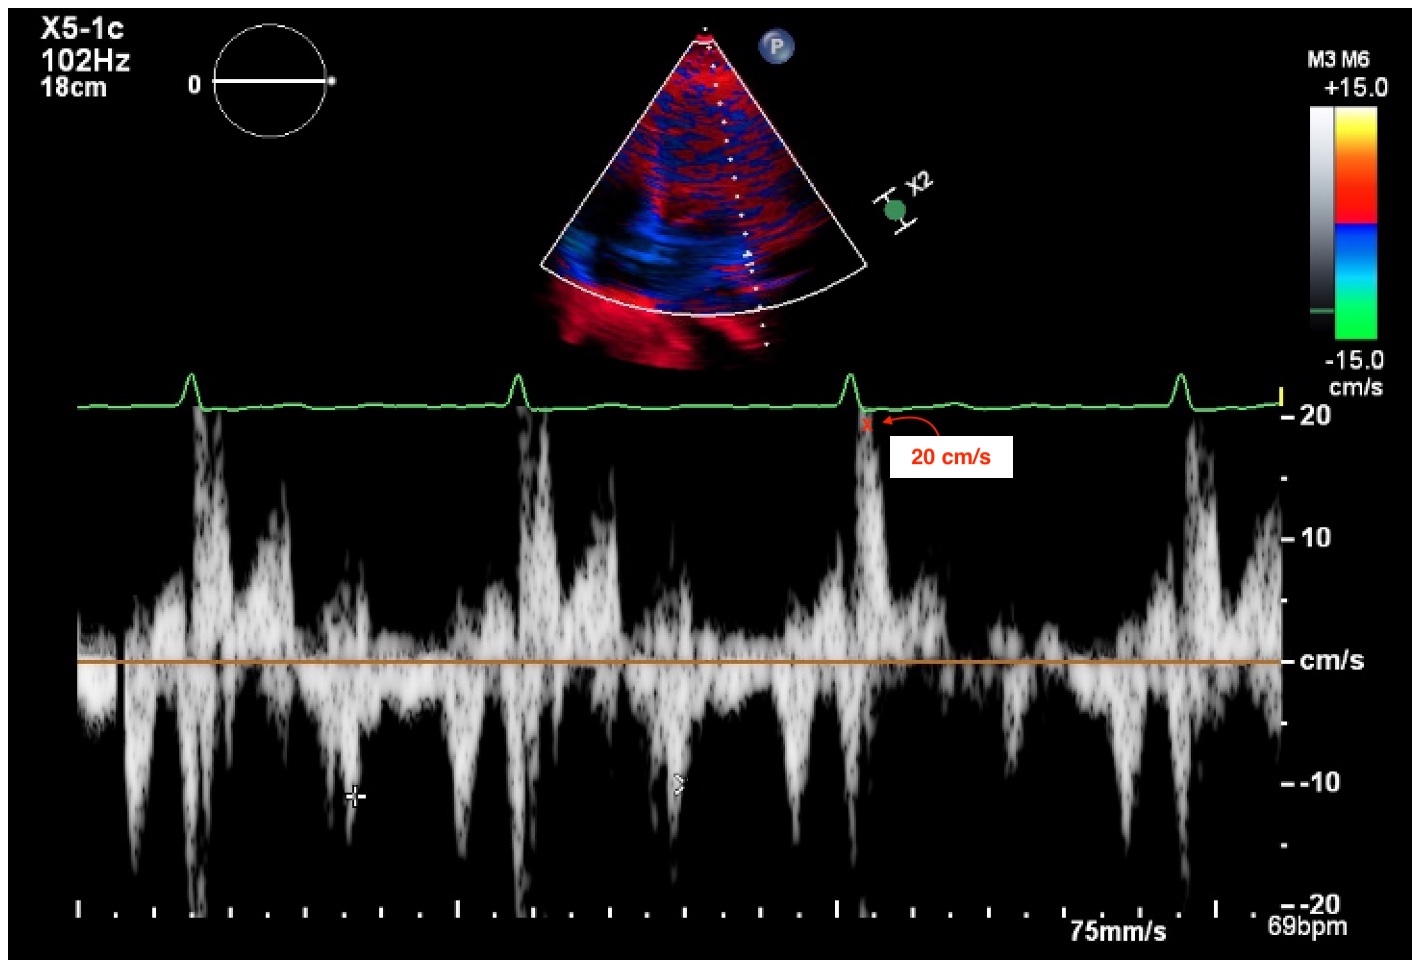

Initial transthoracic echocardiography revealed reduced left ventricular ejection fraction (LVEF) and mitral annular disjunction (MAD), with a peak lateral mid-systolic velocity of 20 cm/s (Figure 1). Left heart catheterization showed normal coronary arteries and a right heart catheterization raised concerns for intravascular volume depletion.

MAD is a recognized substrate for out-of-hospital cardiac arrest. In this patient, the presence of MAD, along with a catecholamine surge from a ruptured ectopic pregnancy and acute hypokalemia from vomiting, likely created a highly proarrhythmic state. High-risk features in MAD associated with arrhythmic events include bileaflet mitral valve prolapse, myocardial fibrosis on CMR, MAD length equal to or >8.5 mm, and peak lateral mid-systolic velocity >16 cm/s. ICD implantation should be considered in patients with these characteristics, particularly those with sustained ventricular arrhythmias.